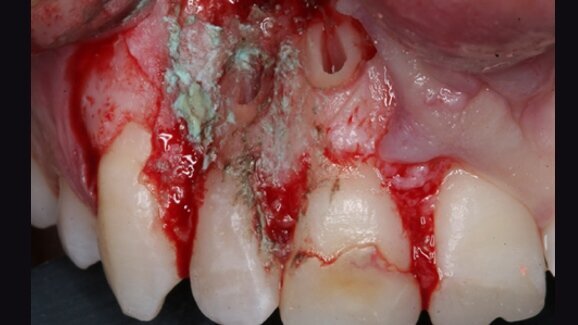

Case presentation: A 15-year-old male patient with a recurrent sinus tract involving the maxillary right incisors was referred for possible treatment with apical surgery. Root canal treatment and apical surgery had been undertaken unsuccessfully one year before. Radiographic examination revealed a radiolucent area surrounding the tooth apexes. A bone block was harvested from the apical area of the central incisor with ultrasound tips to gain access to the root end and apical surgery of both incisors was performed. The bone block graft was used to cover an apicomarginal bony defect of the maxillary lateral incisor. At the three-year follow-up, the teeth had no clinical signs or symptoms, and the periapical radiograph demonstrated complete healing around the apexes.

Conclusions: The use of a bone block graft to treat an apicomarginal defect in conjunction with apical surgery achieved complete healing of the periradicular tissue in this case.